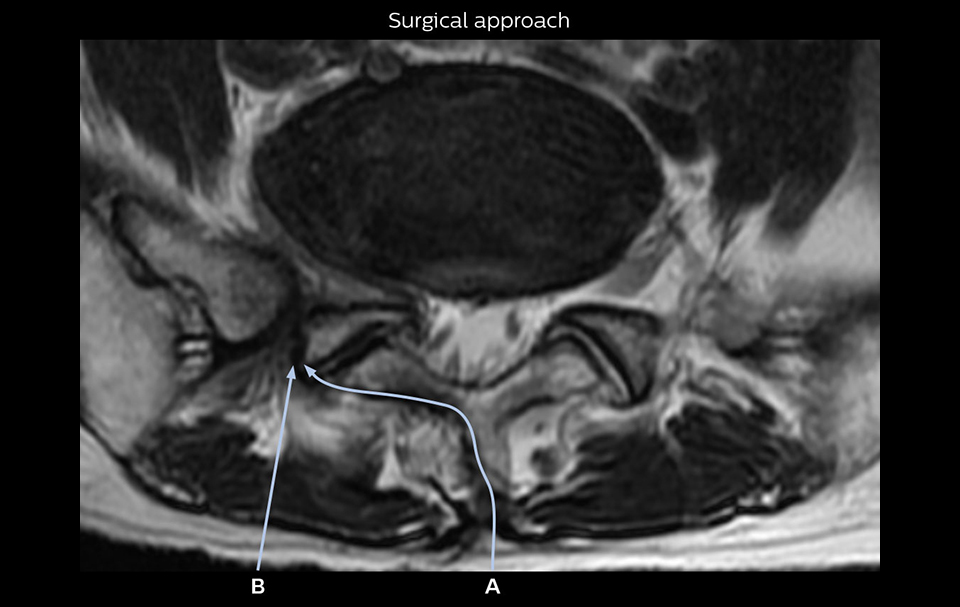

"Because NerveVIEW helps us identify the actual hernia site, it can inform selection of the surgical approach"

“Recently, the two surgical methods extreme and oblique lateral interbody fusion (XLIF and OLIF) have become mainstream for minimally invasive treatment of lumbar spinal canal stenosis and intervertebral foramen stenosis. With these surgical techniques, the spine is approached from the flank, and prior knowledge of the exact anatomy of the lumbosacral plexus would be extremely helpful. To that end, high slice resolution (less than 1 mm acquisition) that enables sharper sagittal MPR images will be needed.”